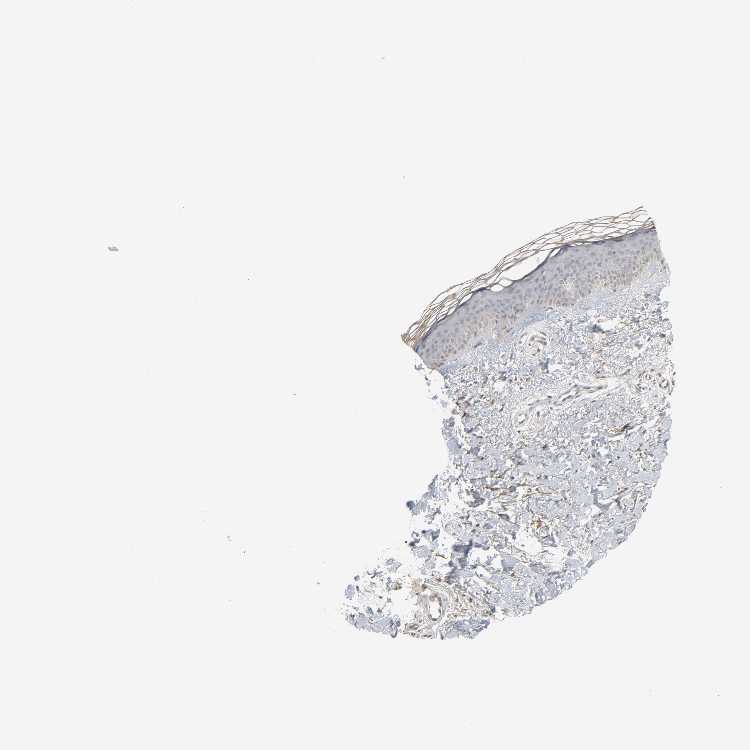

SKIN 1 - Antibody stainingi

Antibody staining in the annotated cell types in the current human tissue is reported as not detected, low, medium, or high, based on conventional immunohistochemistry profiling in selected tissues. This score is based on the combination of the staining intensity and fraction of stained cells.

Each image is clickable and will lead to virtual microscopy that enables deeper exploration of all samples and also displays staining intensity scores, fraction scores and subcellular localization as well as patient and tissue information for each sample.

Antibody HPA004086

Langerhans Not detected

Fibroblasts Medium

Keratinocytes Not detected

Melanocytes Not detected